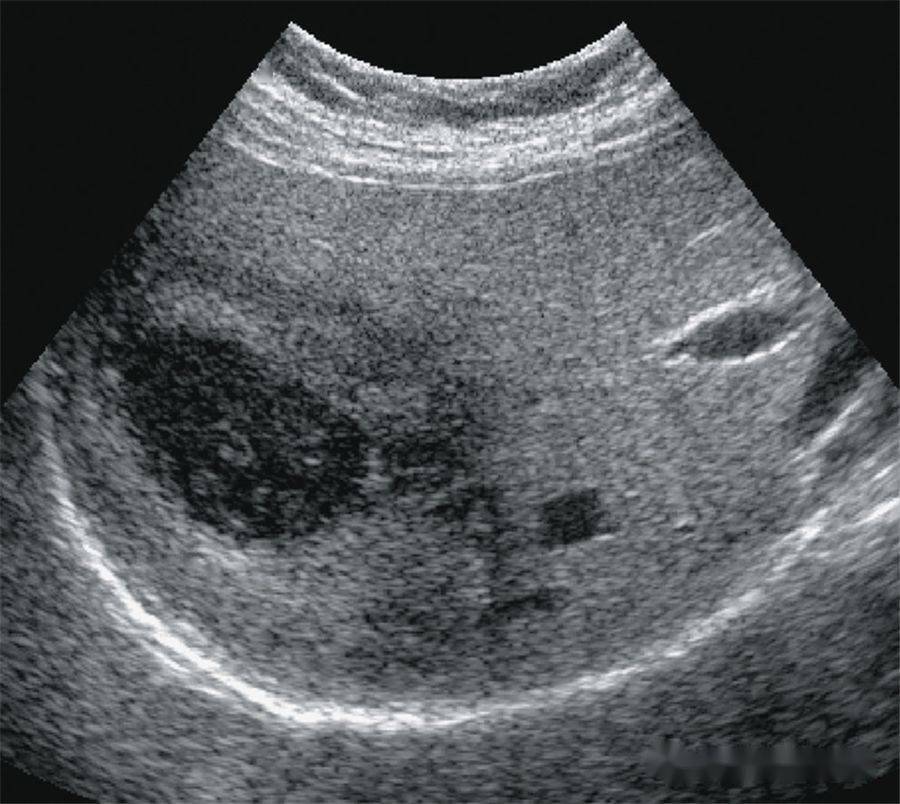

【超声随响】第05期 肝细胞腺瘤 hepatic adenoma

here is small hepatic adenoma, an uncommon benign neoplasm